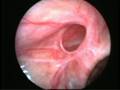

Acute scrotum is sudden onset of redness and swelling over the scrotum. This is associated with severe pain over the scrotum and sometimes lower abdomen and may be accompanied with nausea and vomiting.

Of the many causes of acute scrotum, the most common and important is Torsion of Testis. The testis is supplied by a single blood vessel and any torsion on this vessel may impede the blood supply to the testis. If urgent medical attention and intervention is not done, this may result in testicular gangrene and orchidectomy ( removal of the dead testis) may be needed.

The commonly misleading history given by the parents is that the child may have had a trivial trauma or an insect bite. However, for the clinician the golden rule should be ‘Any acute scrotum is testicular torsion unless proved otherwise’. Investigations like ultrasound and color doppler may be done to help in the diagnosis. However, in the event of any doubt, it is safest to do a surgical exploration of the scrotum. The other uncommon causes of acute scrotum are acute epidydymo orchitis, scrotal abscess, idiopathic scrotal oedema and torsion of appendix of the testis. ●

Acute Scrotum (Right scrotal Abscess)